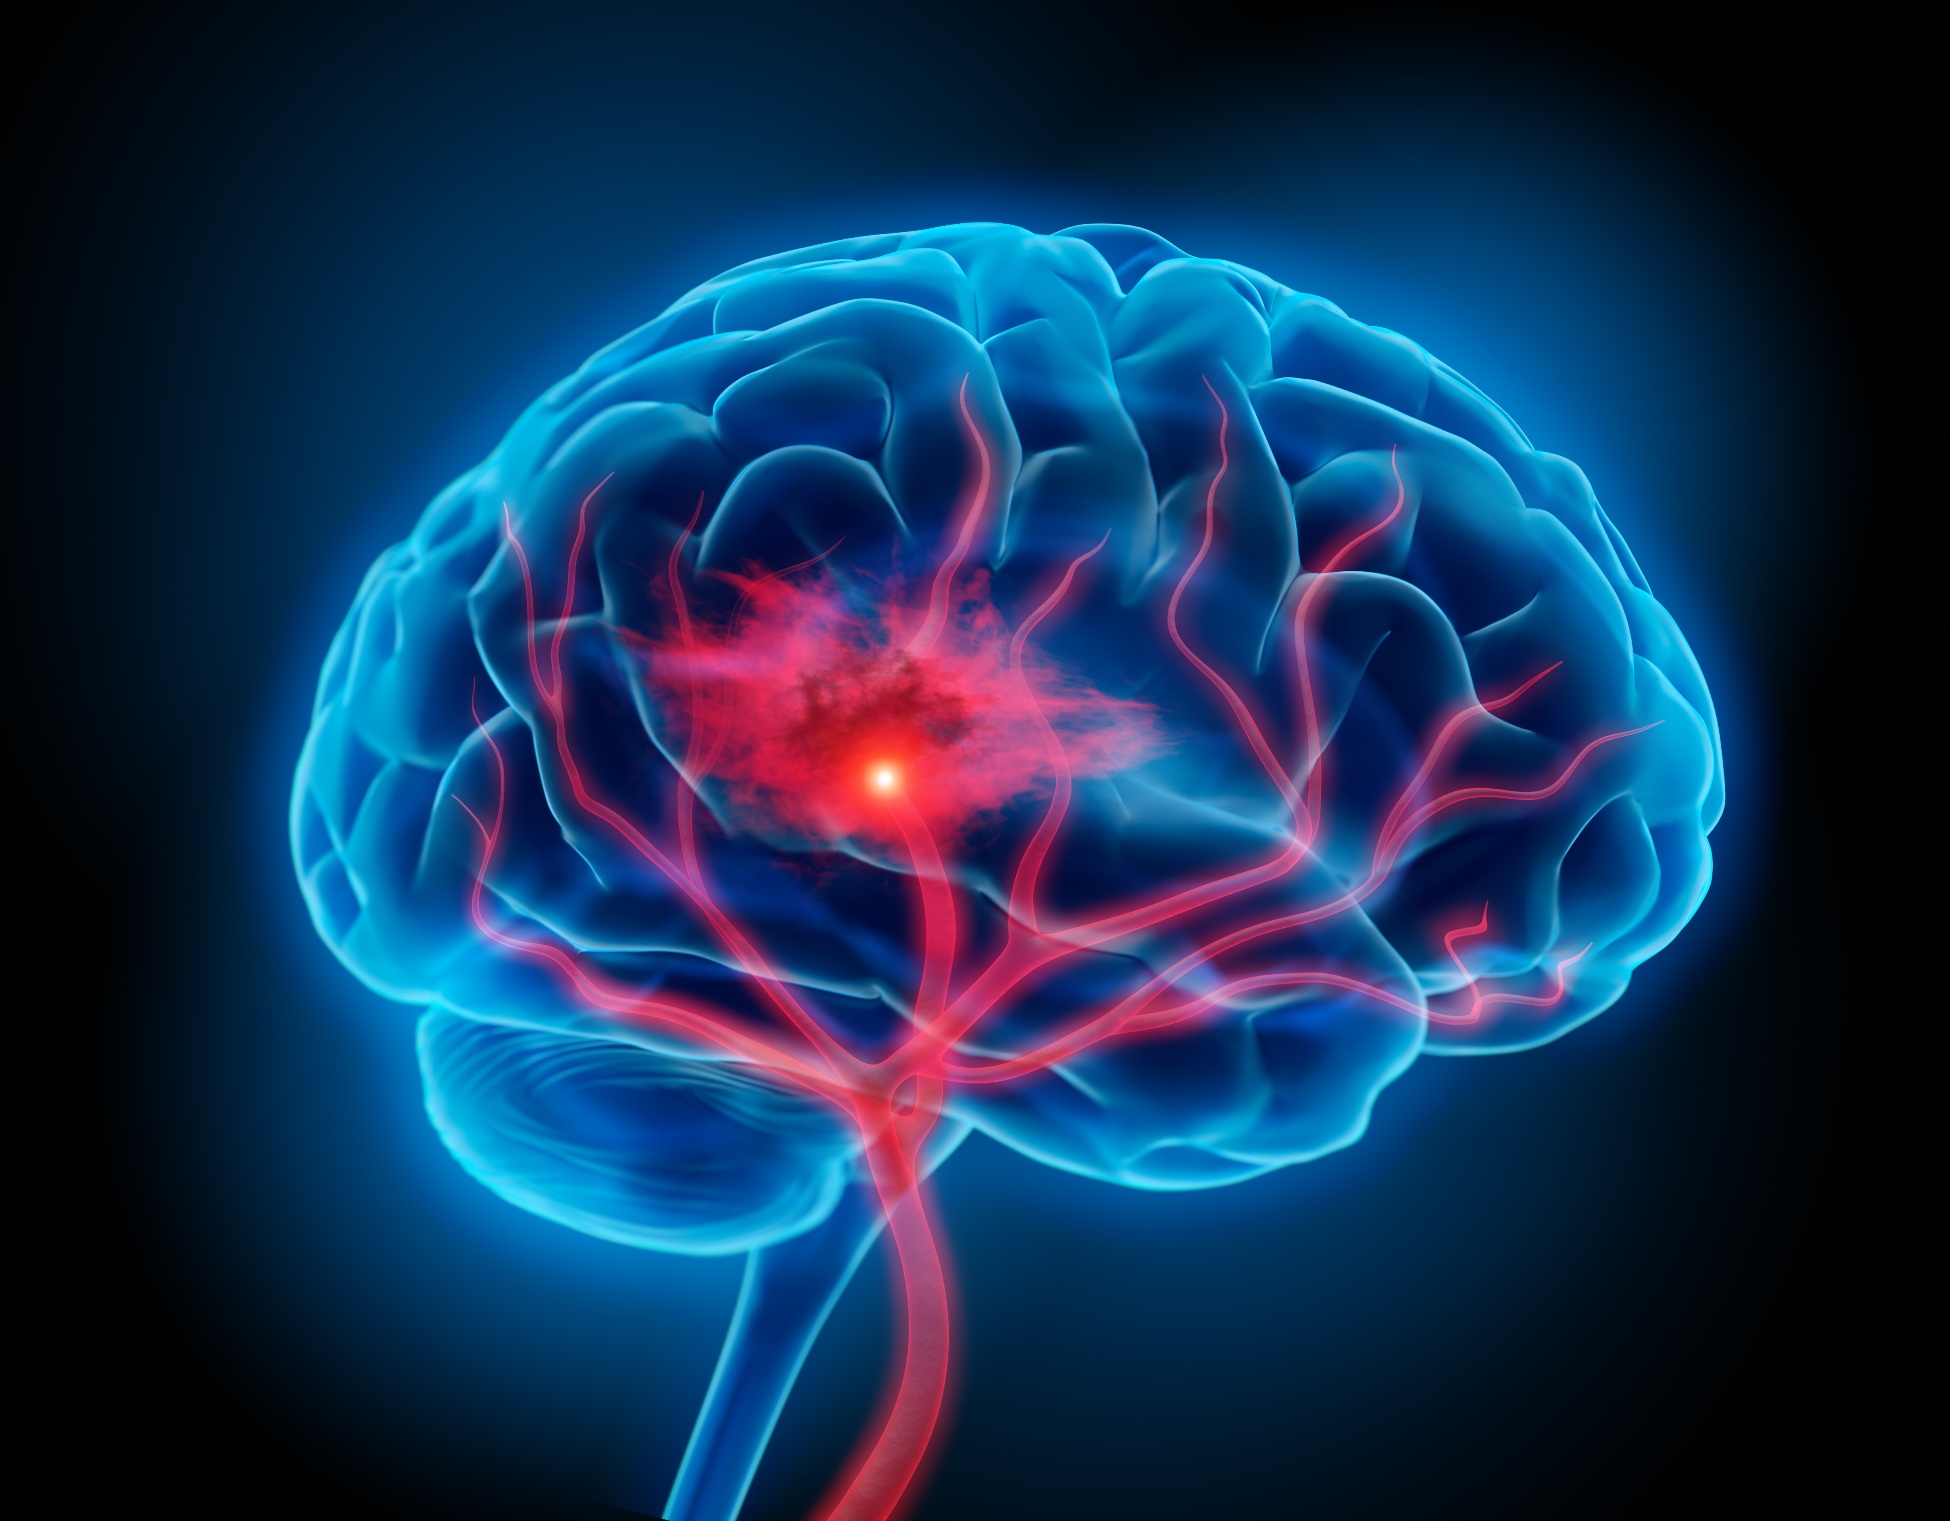

Ann Intern Med, 14 de noviembre de 2017 En pacientes con fibrilación auricular tratados en la práctica médica habitual, las incidencias de accidente cerebrovascular y sangrado con dabigatrán versus warfarina fueron consistentes con las observadas en los ensayos (sin diferencias significativas de tener accidente cerebrovascular isquémico o hemorragia extracraneal, pero con menos probabilidades de presentar hemorragia intracraneal y más probabilidades de tener infarto de miocardio). Los pacientes mayores y aquellos con enfermedad renal tienen tasas de hemorragia gastrointestinal más altas con dabigatrán. La posible relación entre dabigatrán e infarto de miocardio justifica una mayor investigación

En una gran cohorte de EEUU, una cuarta parte de los pacientes con accidente cerebrovascular isquémico e indicación para tPA-IV no recibieron la medicación. Se asoció con edad avanzada y con el sexo femenino, entre otros factores. Neurology, 14 de septiembre de 2016

Según un estudio observacional, los pacientes con ictus isquémico y lesiones pequeñas en la tomografía computarizada de perfusión podrían no beneficiarse con la trombolisis. Annals of Neurology, agosto de 2016

El tratamiento en centros especializados logró mejores resultados en ancianos con ictus, pero la duración excesiva del viaje anuló los beneficios. JAMA Internal Medicine, septiembre de 2016

Se obtienen mejores resultados funcionales en el accidente cerebrovascular isquémico sumando trombectomía al tratamiento médico en las primeras 7,3 horas desde el inicio de los síntomas. JAMA, 27 de septiembre de 2016